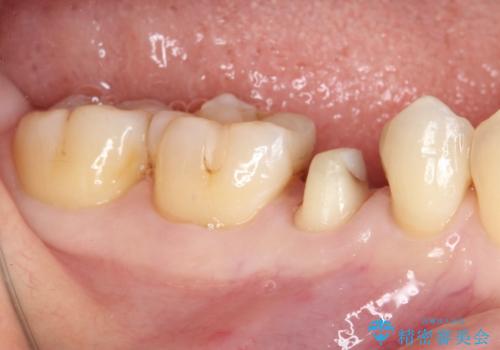

- 他院にて治療した詰め物が欠けてしまった事を主訴に来院された患者様です。

詰め物の範囲が大きく、部分的な詰め物では再び割れてしまうリスクが高いため、

オールセラミッククラウンにて補綴することとしました。